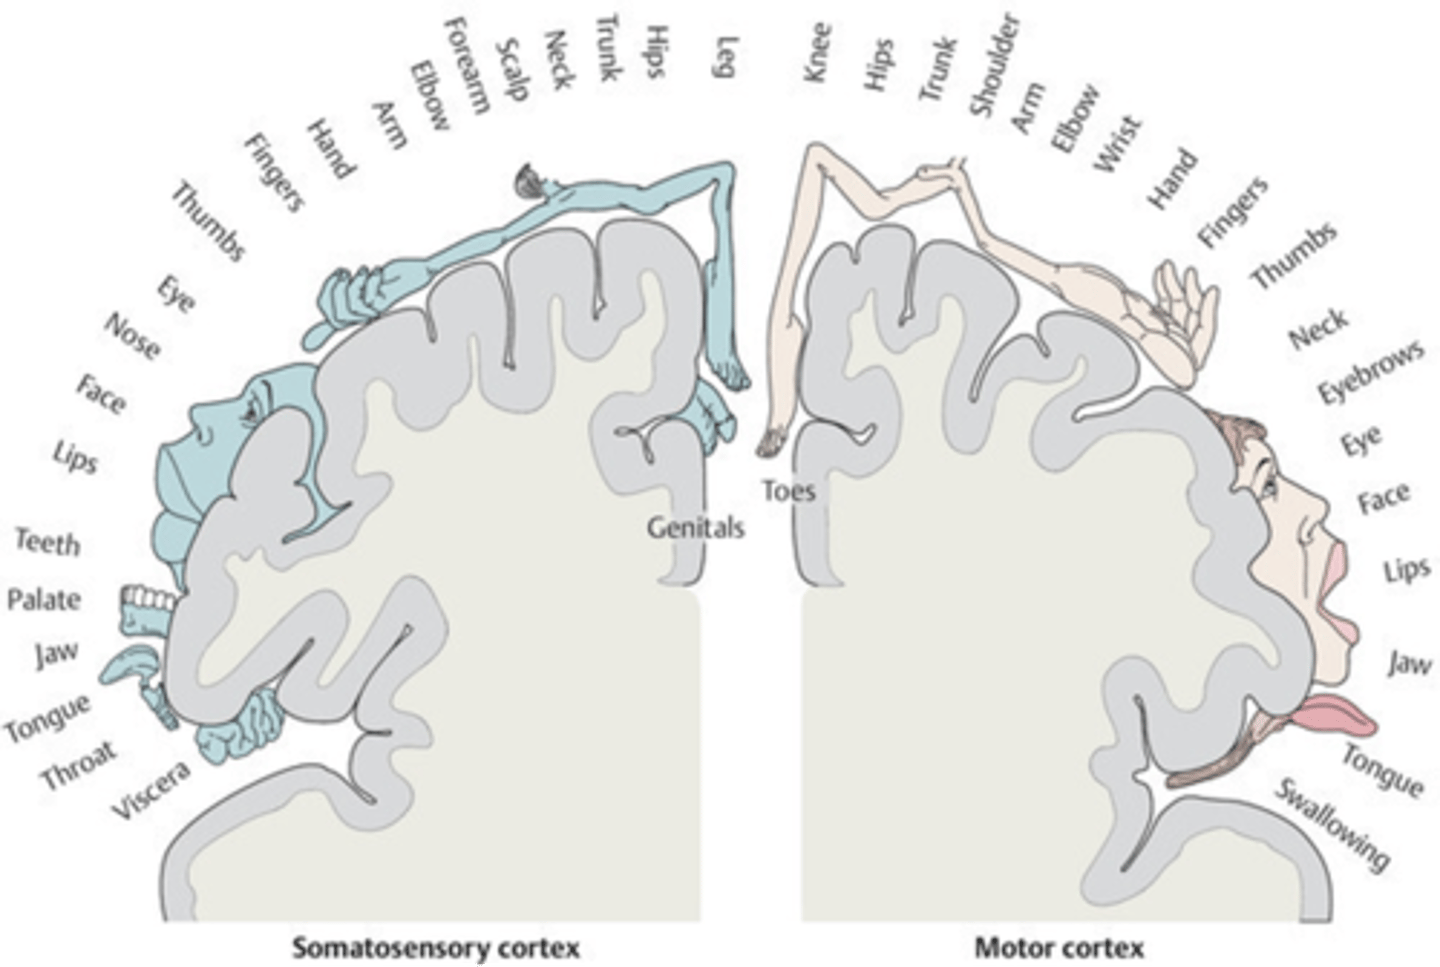

which gyrus is the primary motor complex?

precentral gyrus

which gyrus is the primary somatosensory complex?

postcentral gyrus

what term refers to how a specific part of the body is associated with a distinct location in the CNS?

somatotropy

(t/f) the homunculus is a proportional representation of the human body superimposed on the primary motor and primary somatosensory areas of cortex. areas of greater sensory sensitivity or capacity for finer, discrete movement have a smaller relative degree of cortical representation.

false; areas of greater sensory sensitivity or capacity for finer, discrete movement have a greater relative degree of cortical representation